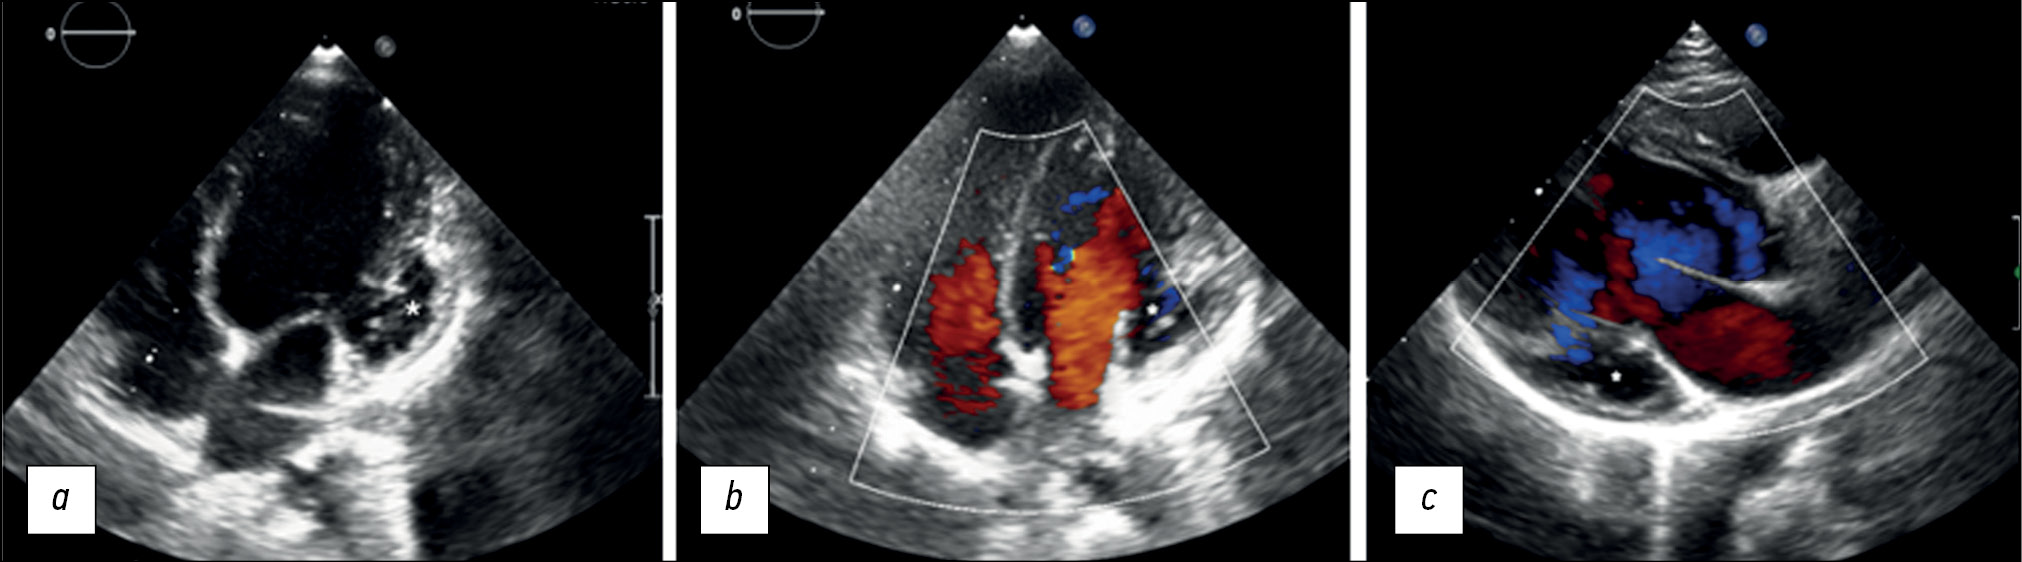

Left ventricular noncompaction with ventricular aneurysm in a 6-year-old patient

Аннотация

Ventricular noncompaction is a rare type of cardiomyopathy often associated with a ventricular aneurysm. We present a clinical case of a 6-year-old female who arrived at our clinic complaining of physical exertion. Echocardiography revealed prominent trabeculations in the left ventricular wall and a lateral-basal part bulging out, indicating noncompaction of the left ventricular myocardium with an aneurysm. With a noncompacted-to-compacted myocardium ratio of 2.6, magnetic resonance imaging revealed the presence of noncompacted myocardium. It also revealed impaired left ventricular systolic function and a left ventricular aneurysm with myocardial scarring. Coronary angiography ruled out coronary artery disease. Therefore, myocardial scarring was caused by noncompacted myocardium microcirculatory disorder.